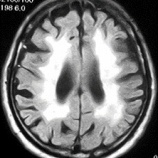

血圧管理の厳格化が脳血管性認知症を減らしている

[[img(https://care.blogmura.com/ninchisyou/img/ninchisyou88_31.gif)]] [https://care.blogmura.com/ninchisyou/ranking.html にほんブログ村 介護ブログ 認知症へ(文字をクリック)] 2025年8月に6年ぶりに「高血圧管理・治療ガイドライン」が改訂されました。今回